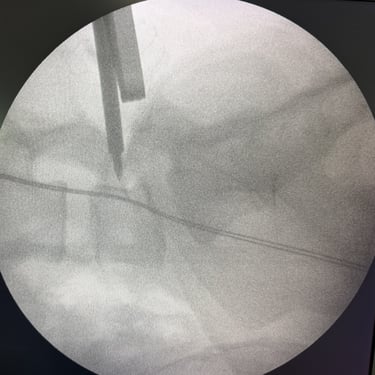

Listesis Lumbar L5–S1 por Fractura Ístmica: Estabilización con FTP y TLIF

La listesis lumbar L5–S1 por fractura ístmica se produce por un defecto en la pars interarticularis que genera inestabilidad vertebral, dolor lumbar crónico y compromiso radicular. Cuando el tratamiento conservador no es efectivo, la artrodesis lumbar con fijación transpedicular (FTP) asociada a la fusión intersomática transforaminal (TLIF) es una alternativa quirúrgica eficaz. Este procedimiento permite descomprimir las raíces nerviosas, restaurar la alineación vertebral y lograr una fijación sólida del segmento afectado. La combinación de estabilización y fusión reduce el dolor, mejora la función y favorece una recuperación segura y progresiva.